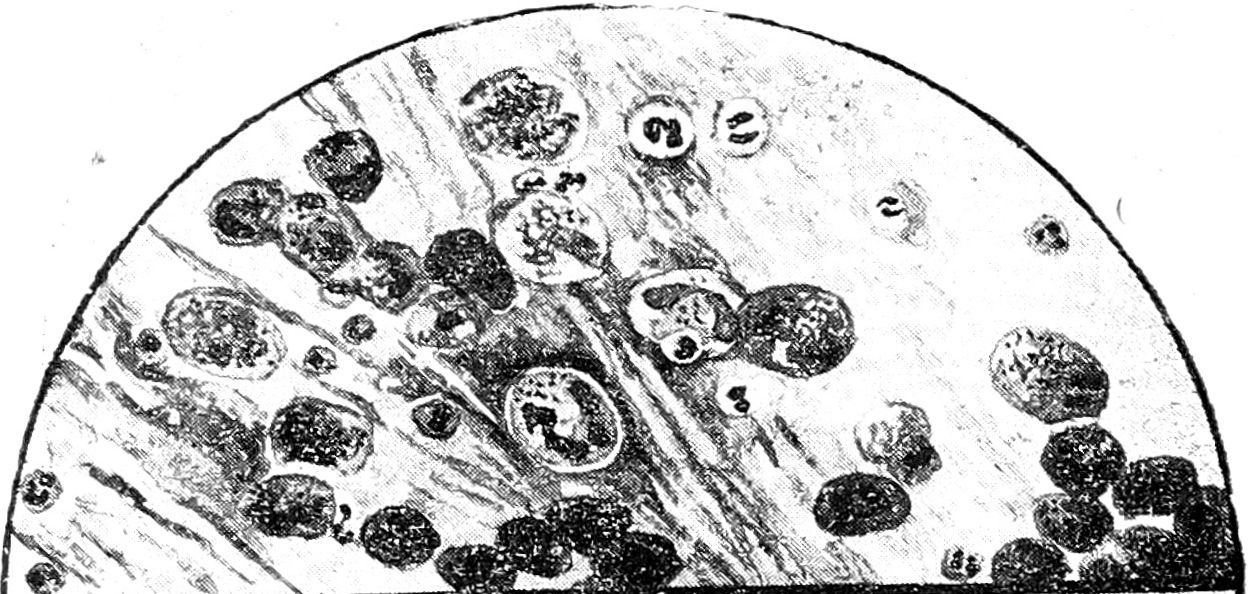

Рис. 1. Vitium cordis и застойные явления в легких. Слизистый фон с пузырьками воздуха, N, много AM.

Общие свойства окраски всех этих клеток, наличность переходов между ними, появление их при заинтересованности альвеол и отсутствие в случаях чистых бронхитов (где паренхима легких не затронута)—все это говорит за то, что перечисленные элементы одного происхождения, находятся в зависимости от состояния альвеол и представляют собою ничто иное, как клетки альвеолярного эпителия, изменившиеся под влиянием раздражения и приобревшие гистиоцитарные свойства.